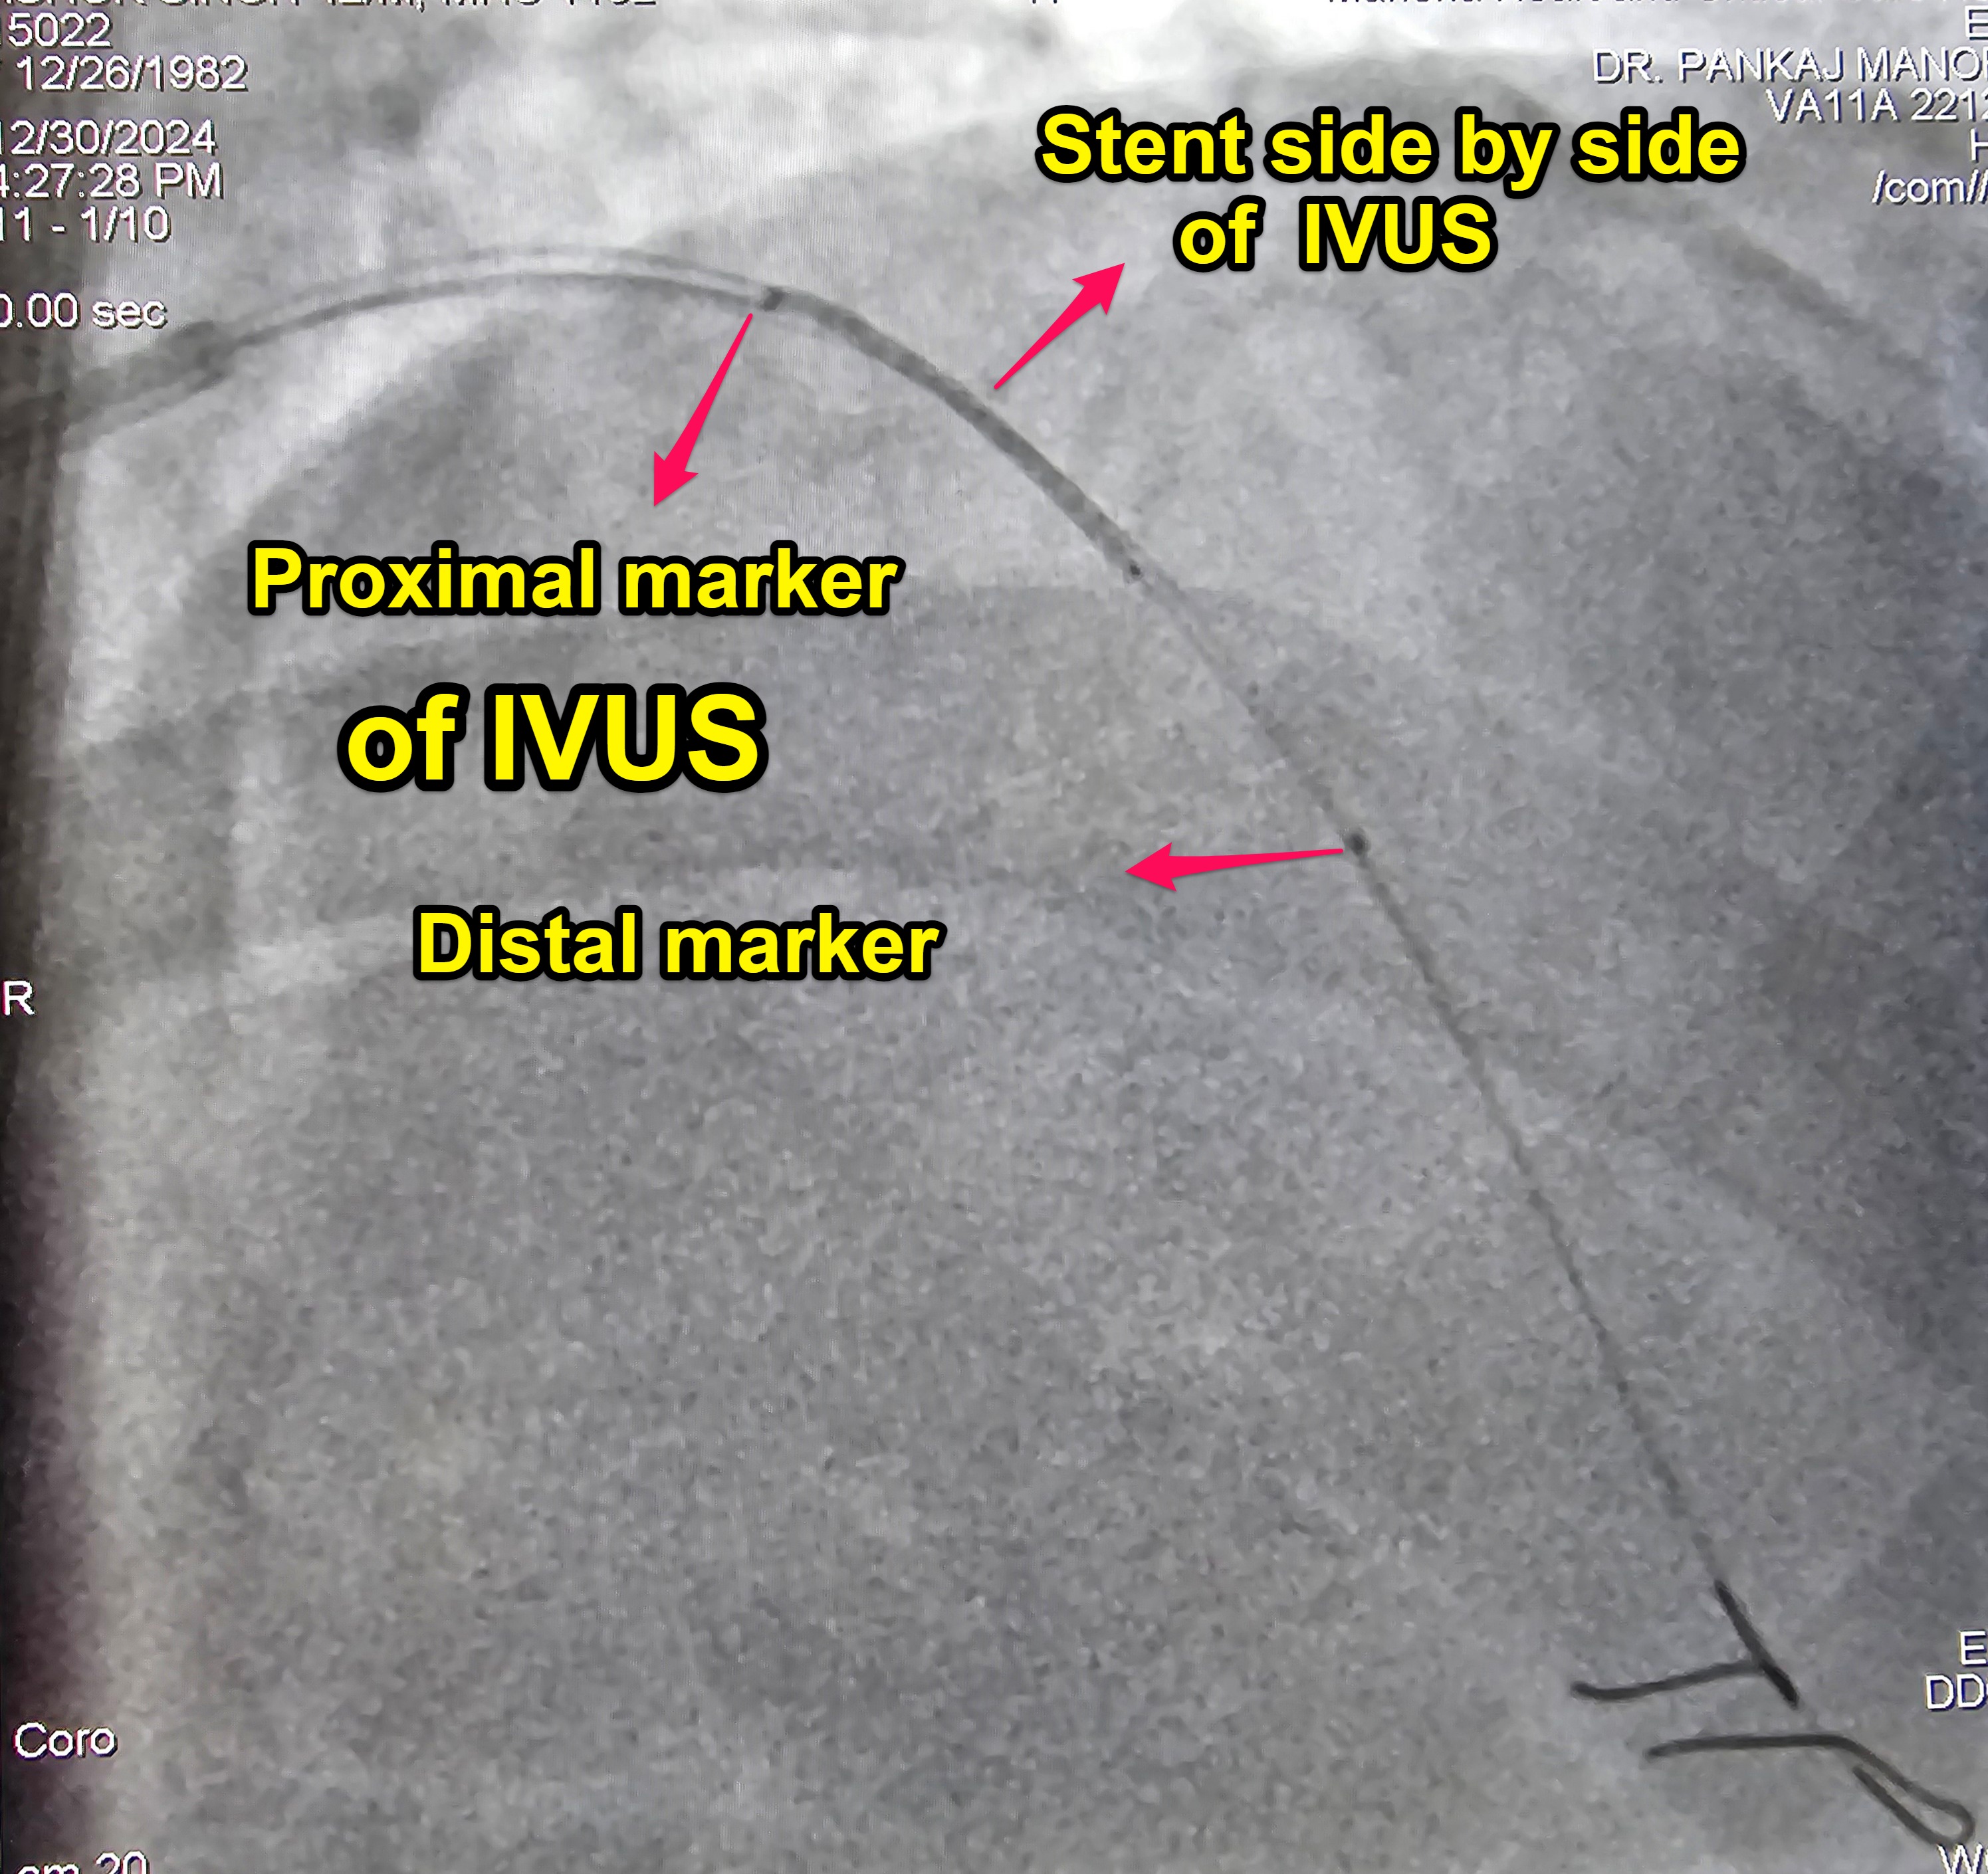

llllStep 1: Take 8F guiding catheter Step 2 : No contrast puffing for catheter Engagement . You can confirm catheter engagement by 3 ways Step 3 : Take 2 wires. No contrast puffing for wiring . Use reference image as rodemap Step 4 : Stent Sizing By IVUS Step 5 : Park the IVUS in the proximal landing zoneStep 6 : Take the stent on another wire & place it exactly side by side to the IVUS (which is the proximal landing zone already marked by the IVUS)..Step 7 : Confirm the landing zone again by doing live IVUS with the stent side by side.Step 8 : Pull the IVUS and its wire. Step 9 : Deploy the stent.